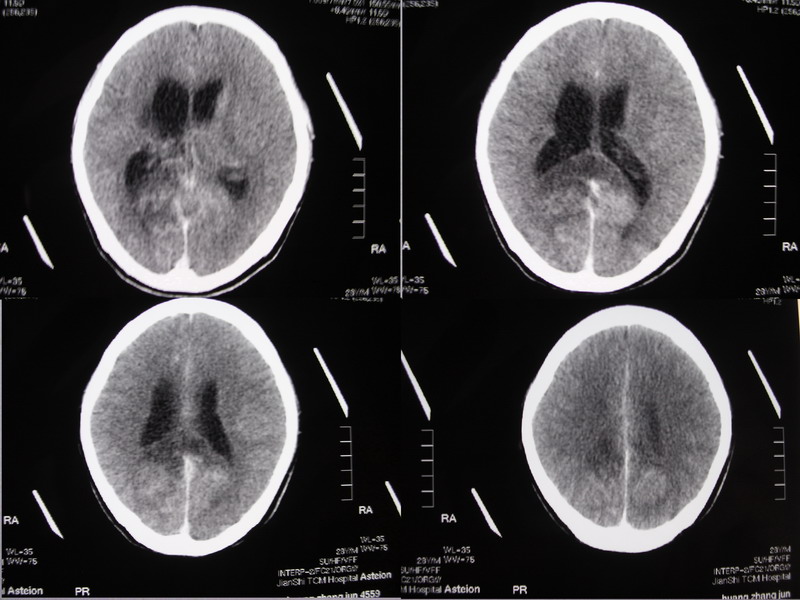

以下是引用余辉在2007-5-14 17:03:00的发言:[br]右侧脑室颞极后方可见高密度块状影,颞极呈杯口状推挤前移,右侧大脑脚及丘脑上部受推挤向对侧移位,右丘脑区结构紊乱,增强扫描病灶有不规则强化,以下部颞极后方为著。胼胝体压部及右枕叶视辐射区低密度改变,右基底节区低密度改变,双侧脑室不对称积水征象,意见:1颞极后方—右丘脑区占位性病变,如室管膜瘤等2脑血管疾病如moyamoya,局部脑血管畸形等3脑膜炎等后遗改变,建议mr及脑血管造影检查[br][br][本贴已被 余辉 于 2007-5-14 17:05:26 修改过]

以下是引用ssmmxx在2007-5-14 18:05:00的发言:[br]颞极后方—右丘脑区占位性病变,如室管膜瘤等2脑血管疾病如moyamoya,局部脑血管畸形等

以下是引用qiuleiyu在2007-5-14 18:43:00的发言:[br]支持;1,交通性脑积水(病脑后遗征?)2,右基底节及胼骶体压部低密度灶伴轻度占位表现,结合年龄考虑moyamoya,建议dsa.[br]